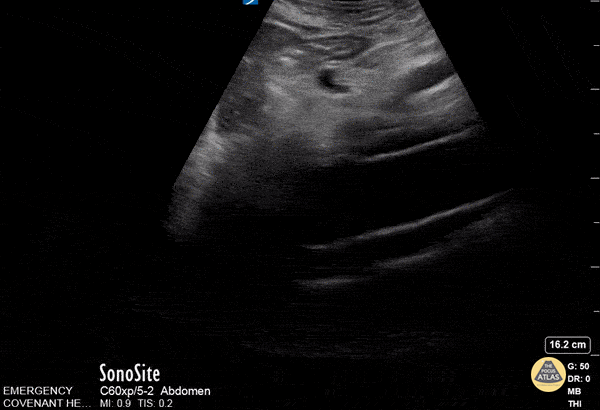

Aorta - Thoracic Aortic Dissection

Approximately 70 year old male with history of AAA repair presented after an episode of syncope. POCUS performed in the ED revealed a dissected intimal flap and false lumen. CT confirmed the finding of thoracoabdominal aortic dissection. David Hansen, DO Matthew Wolf, MD Therese Mead, DO, RDMS, FACEP Central Michigan University